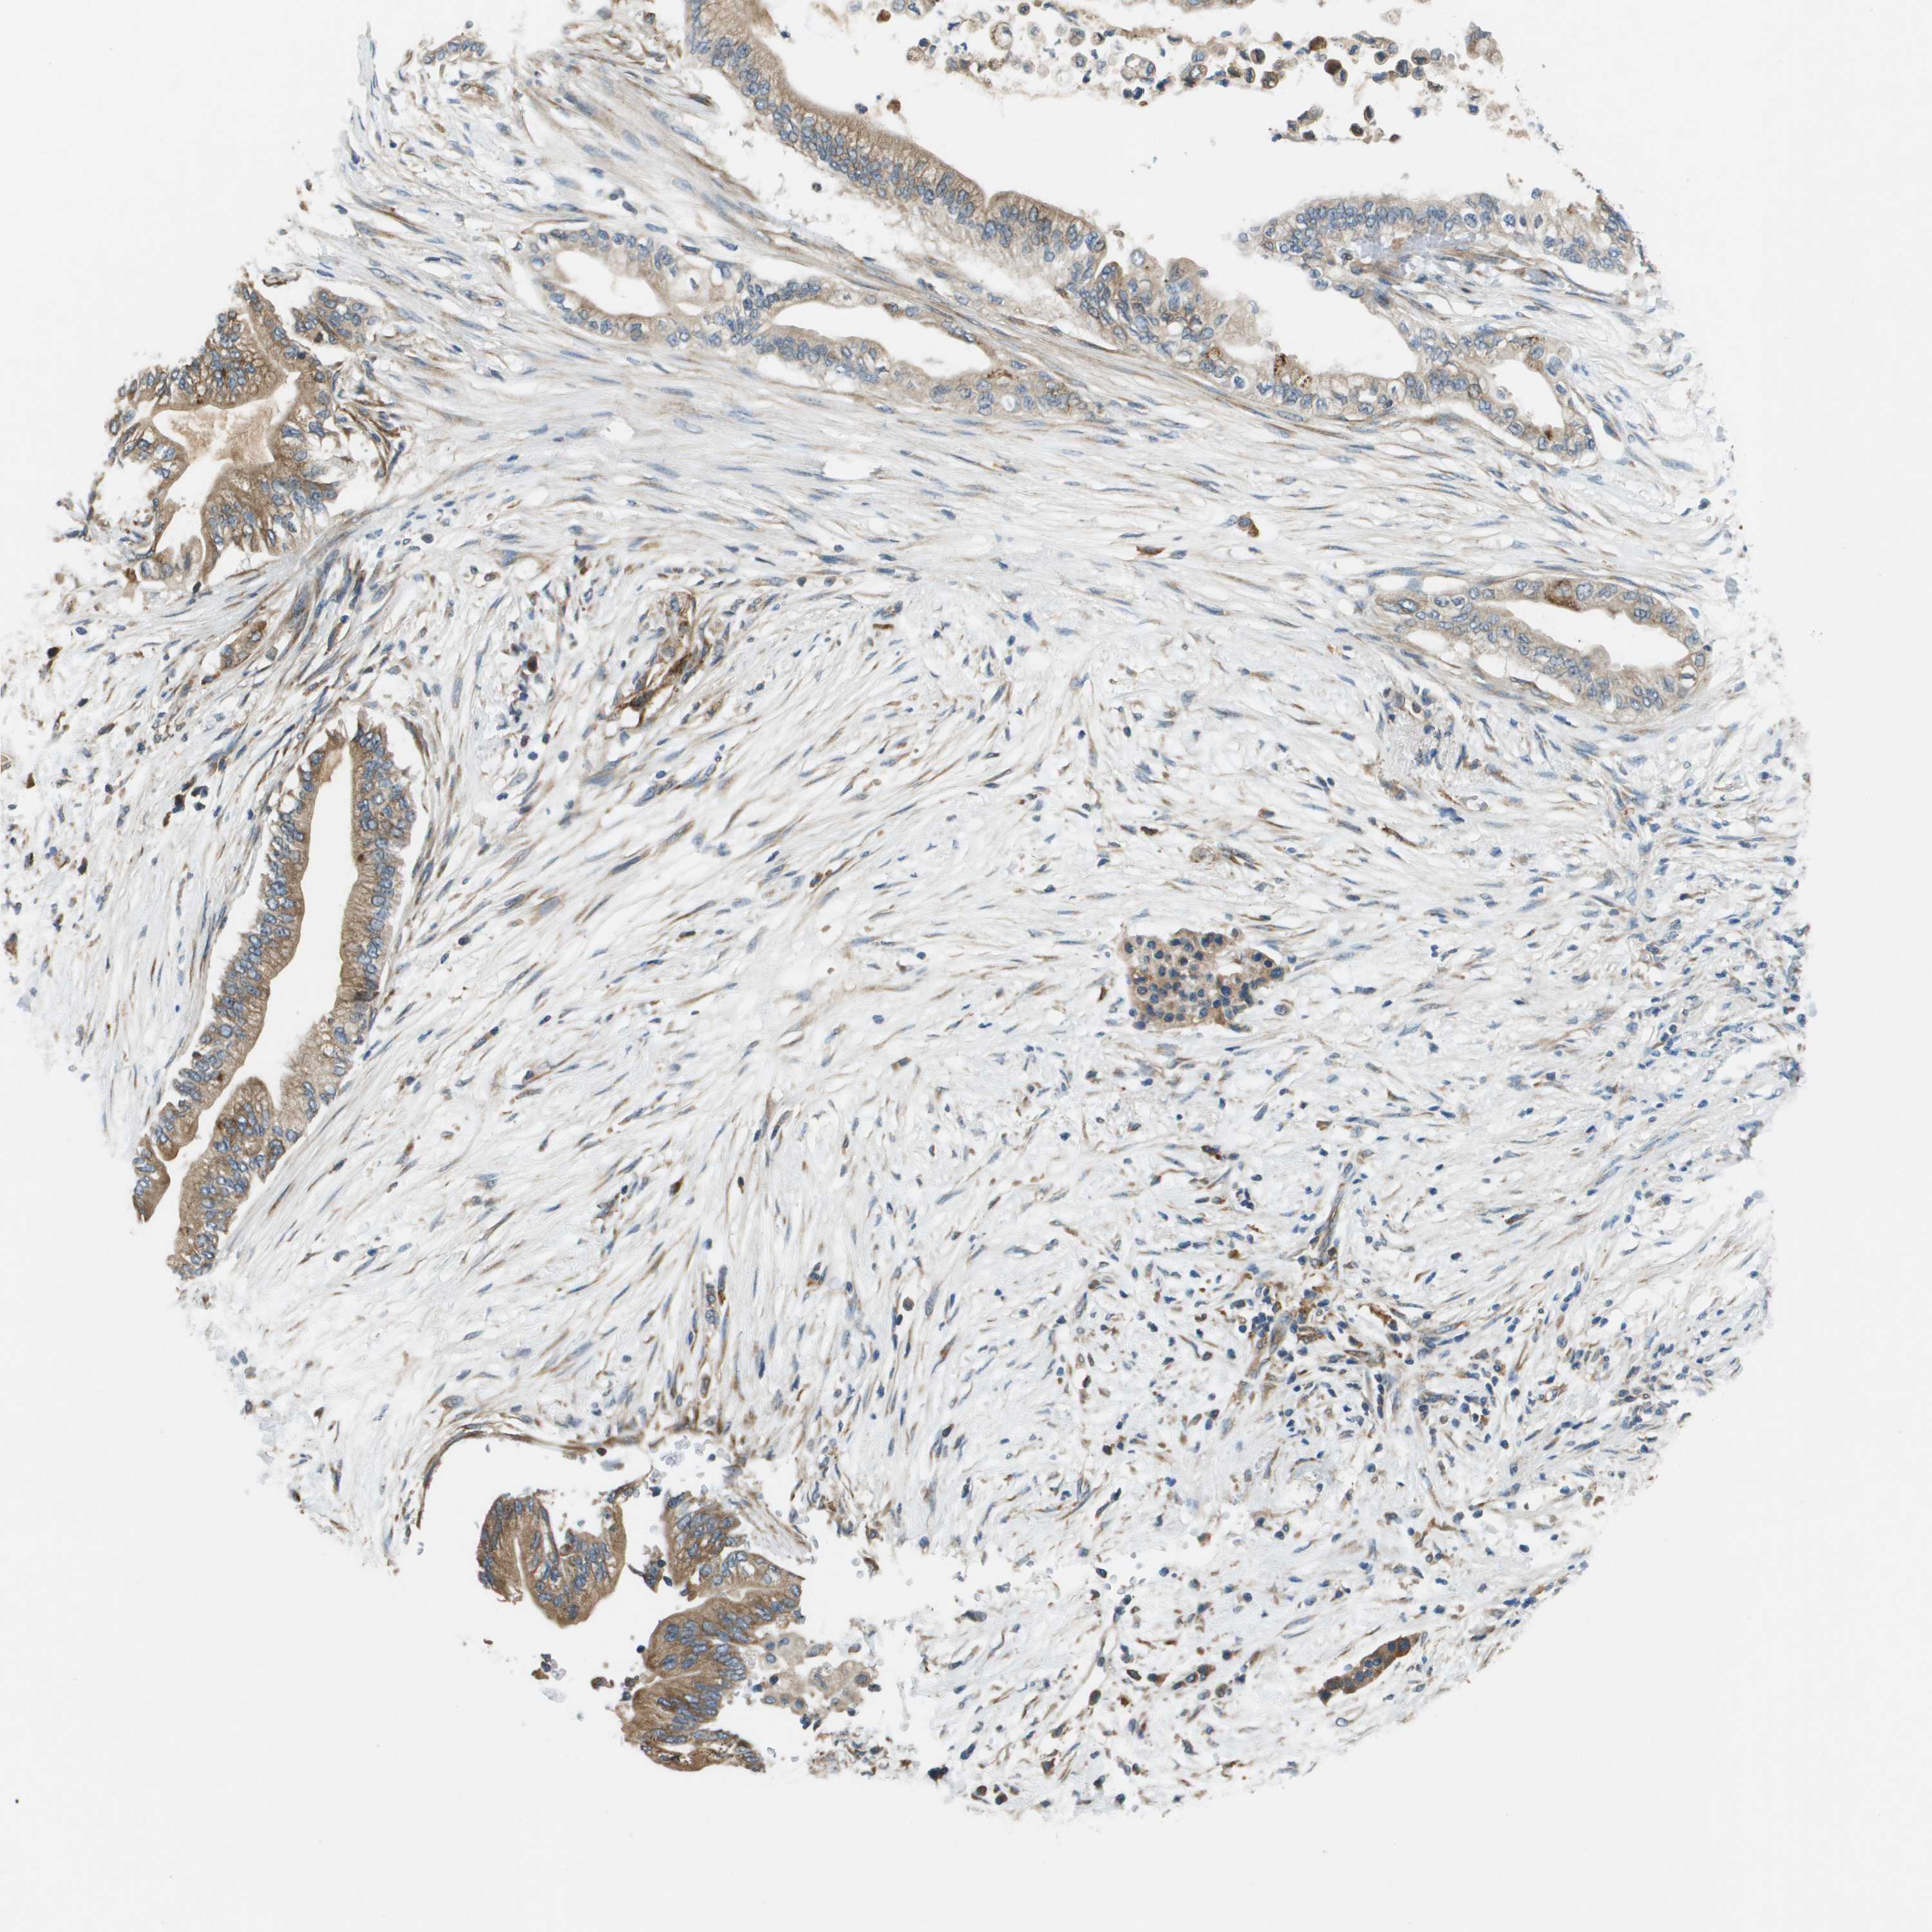

PANCREATIC CANCER - Protein expressioni

A mouse-over function shows sample information and annotation data. Click on an image to view it in a full screen mode. Samples can be filtered based on level of antibody staining by selecting one or several of the following categories: high, medium, low and not detected. The assay and annotation is described here.

Note that samples used for immunohistochemistry by the Human Protein Atlas do not correspond to samples in the TCGA dataset.

Antibody stainingi

Antibody staining in the annotated cell types in the current human tissue is reported as not detected, low, medium, or high, based on conventional immunohistochemistry profiling in selected tissues. This score is based on the combination of the staining intensity and fraction of stained cells.

Each image is clickable and will lead to virtual microscopy that enables deeper exploration of all samples and also displays staining intensity scores, fraction scores and subcellular localization as well as patient and tissue information for each sample.

Antibody HPA010645

Antibody HPA017055

Antibody HPA046639

Staining

High

Medium

Low

Not detected

Intensity

Strong

Moderate

Weak

Negative

Quantity

>75%

75%-25%

<25%

None

Location

Nuclear

Cytoplasmic/membranous

Cytoplasmic/membranous,nuclear

Adenocarcinoma, NOS

Adenocarcinoma, metastatic, NOS